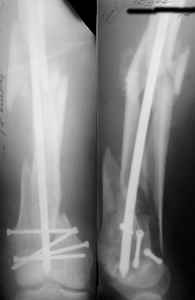

Attached are few examples from our Hospital:

A. Difficult reductions, even in retrograde nailing (my preference, easier control of "small" distal fragment) and it is much, much harder to do it anterograde (Alex, do you have one good case in your collection of anterograde nailing in very distal fractures - as you have suggested that I

should have done it in my previously posted case?

Malpositioning is much too common (recurvatum, varus - valgus).

B. Fixation loosening: distal cutting of the nail, non-unions do happen (cases attached).

Locking Plating has more distal screws than any nail, fixed angles and provides much better fixation, especially in osteoporotic bone.